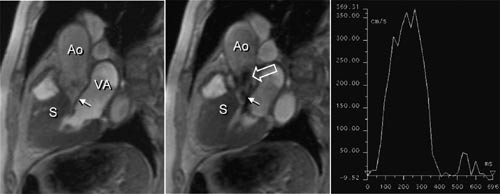

Kardiomyopati

Den primære bildediagnostiske utredningen av kardiomyopati gjøres vanligvis med ekkokardiografi, men MR kan gi viktige bidrag ved flere typer av kardiomyopati. Fordi MR ofte gir en mer nøyaktig fremstilling av venstre og høyre ventrikkels veggtykkelse enn ekkokardiografi og en sikrere fremstilling av arrområder, kan metoden sannsynligvis sikrere skille mellom idiopatisk dilatert kardiomyopati og ventrikkeldilatasjon pga. iskemisk hjertesykdom. Ved hypertrofisk kardiomyopati kan MR vise den nøyaktige distribusjon av veggfortykkelsen og også avsløre og kvantitere en eventuell obstruksjon i utløpstractus av venstre ventrikkel (fig 3). Mitral insuffisiens, som ofte er til stede ved denne tilstanden, kan også påvises og kvantifiseres. Ved restriktiv kardiomyopati er en aktuell differensialdiagnose konstriktiv perikarditt. Ved sistnevnte sykdom kan MR påvise fortykket perikard.

Klaffefeil

Det er sjelden indikasjon for å gjøre MR-undersøkelse ene og alene for å evaluere klaffefeil, som regel kommer man til målet med ekkokardiografi. Når dette mislykkes, kan imidlertid MR være en god erstatning (15). MR-opptak som viser hjertets kontraksjoner og normalt sirkulerende blod med kraftig signal («hvitt blod») – såkalt cine-MR – vil vise høye blodstrømshastigheter og turbulens som bortfall av signal (fig 3). En klaffestenose ses derfor som en sort dusj (i det ellers hvite blodet) på medstrømssiden av klaffen, mens en insuffisient klaff ses som en sort dusj på motstrømssiden av klaffen (3, 4). Både stenoser og insuffisienser kan kvantifiseres.